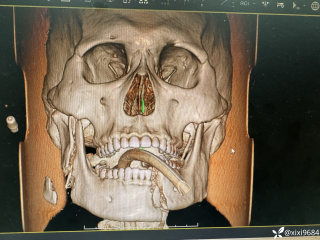

整个右侧胸腔被滚烫的铝水烧穿,多根肋骨骨折、碳化、坏死,背腹部和面部也有大面积烧伤……右肺完全暴露在外,被压缩到只剩一半的体积。这样的病人,还救得活吗?300℃ 铝水烧了 10 分钟,整个右胸都烧穿了时间拨回到 2024 年 9 月 26 日,下午 15 点,救护车的警笛声撕破了浙江大学医学院附属第二医院(文内简称「浙大二院」)解放路院区的平静。警笛声由远及近,停在了急诊的门口。不多时,一群人冲进急诊。「300 多度的铝水烧了 10 分钟,整个右胸都烧穿了!」负责转运的同事几乎是咆哮着喊出这句话。急诊医学科的许永安主任医师看到患者情形时,心下一惊。本该完整的右侧胸腔,现在成了一个焦黑的大洞,大